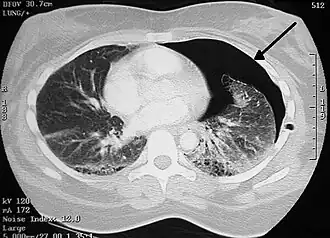

Tomografía axial computarizada

Aunque el TAC supone el gold standard en la detección de neumotórax, superando en sensibilidad y especificidad a la radiografía,[41] generalmente este no se necesita para establecer el diagnóstico de neumotórax, pero puede resultar de utilidad en situaciones particulares. En algunas patologías de las vías respiratorias, y especialmente en presencia de enfisema, es posible que ciertas estructuras pulmonares (como las cavitaciones) tengan la misma apariencia que un neumotórax en la radiografía, en cuyo caso el tratamiento específico de neumotórax no está indicado.[20] En ciertos casos de traumatismo el paciente es incapaz de permanecer en posición vertical durante la realización de la radiografía, lo cual dificulta la identificación del neumotórax en la imagen. Para estas situaciones, el TAC puede indicarse al poseer una mayor fiabilidad.[29]

Otro uso del TAC es para la identificación de lesiones concomitantes, ayudando a detectar bullas o lesiones quísticas en casos de neumotórax primario, y como herramienta de búsqueda de la causa de origen en el neumotórax secundario.[20][31]